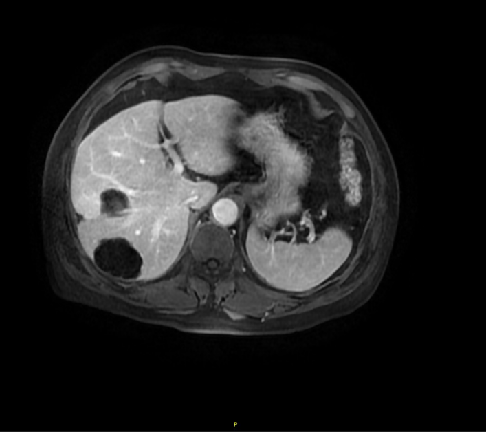

影像学检查:

腹部CT:

检查时间:(2017-4)

影像图谱:肝内占位,考虑为肝细胞Ca肝内转移可能